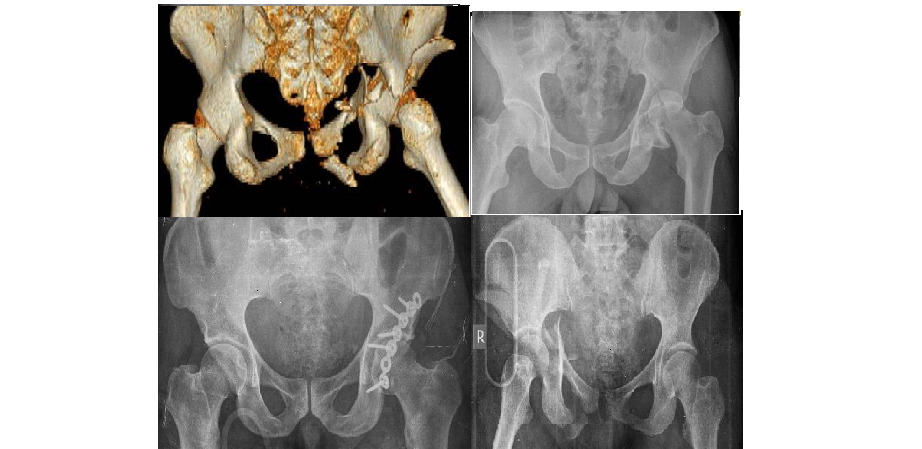

ASETABULUM KIRIKLARI

Doktor Mehmet Subaşı

Kalça, yuva-top şekli bir eklemdir. Topu oluşturan yapının femur ...